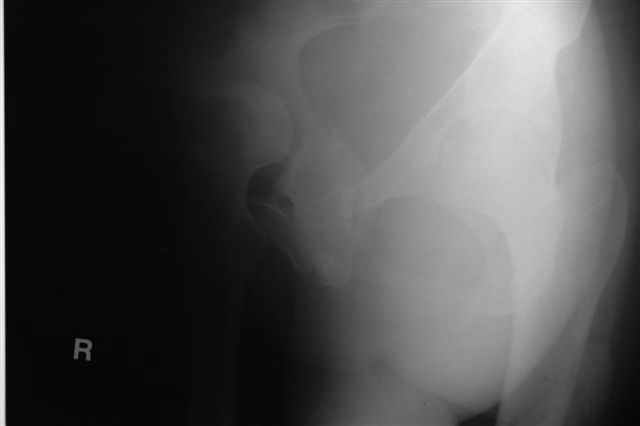

Трудности возникли сразу после рассечения большой ягодичной мыцы - короткие наружные ротаторы едва ли определялись - головка и шейка (как видно на

снимке) ушли в таз, пришлось воспользоваться дистрактором( ручные попытки выдернуть голову из под проксимального фрагмента - безуспешны) Шарнирный дистрактор - великое изобретение, без него репозиция была просто невозможна.

> Трудности возникли сразу после рассечения большой ягодичной мыцы - короткие

> наружные ротаторы едва ли определялись - головка и шейка

> ( как видно на

> снимке) ушли в таз, пришлось воспользоваться дистрактором

P.S. в приложении R пациентки с похожей проблемой доступа.. за исключением того, что перелом

двухколонный. Вертлугу лечили Y доступом.